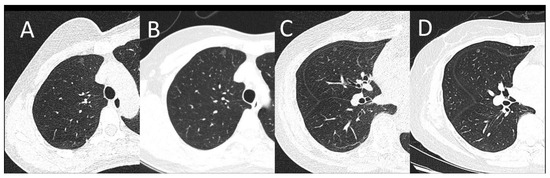

There is no detection efficacy difference between the SDCT and LDCT groups. The CT values of recognizable nodules in the LDCT group ranged from −853.9 HU to 7.2 HU, and nodule sizes ranged from 3.8 mm to 15.5 mm. While the CT values of identifiable nodules in the SDCT group ranged from −753.9 HU to 6.2 HU, and their sizes varied from 3.8 mm to 15.5 mm. No significant difference was observed between LDCT and SDCT in terms of the diameter or CT values of pulmonary nodules (p > 0.05) (Table 3). The identification performance of small pulmonary nodules of LDCT and SDCT is shown in Figure 2.

Figure 2.

(A,B): A female patient with a BMI of 20.31 kg/m2. A subpleural pulmonary nodule was shown on LDCT (A) and SDCT at the same location as A (B). (C,D): A female patient with a BMI of 24.91 kg/m2. One pulmonary nodule can be seen on LDCT (C) and SDCT at the same location as C (D). Images of both protocols can clearly show the lesion. The image noise was appreciably increased on LDCT images, however, there was sufficient contrast between the nodule and the adjacent lung tissue for lesion identification.